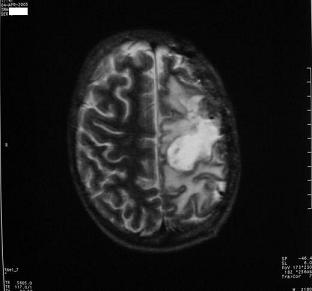

До реабилитационного лечения

Компьютерная томограмма мозга больного К

до реабилитационного лечения.